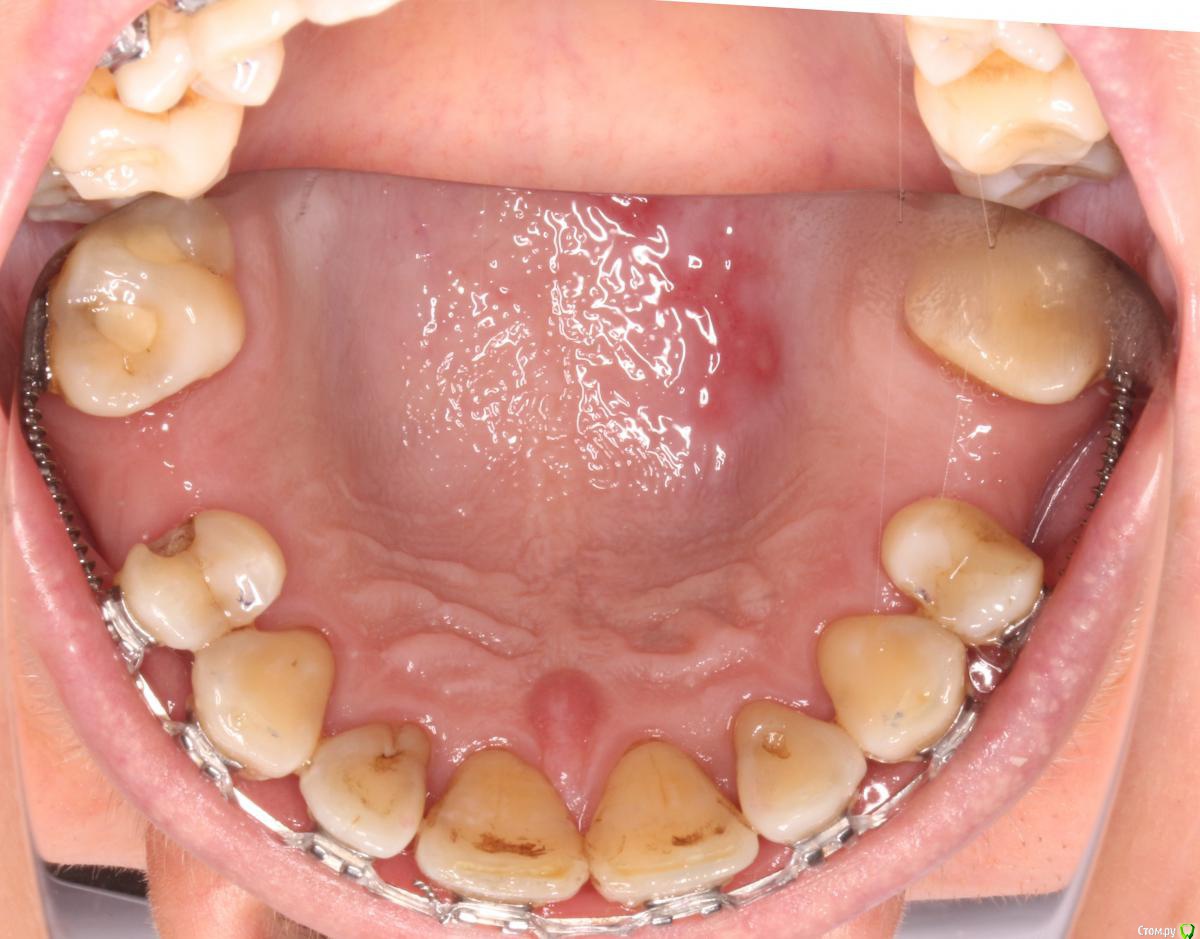

Yana guapa Опубликовано 16 марта, 2016 Поделиться Опубликовано 16 марта, 2016 достаточно обычной пластинки Hawley. только чтобы базис не касался слизистой в области отст-х зубов (чтобы не было большей резорции кости). или каппа. Все это носить достаточно на ночь. (на остальные зубы конечно несъемный ретейнер, в том случае с 4 по 4ку). Иногда клею проволоку с вестибулярной и небной поверхности (сталь 21*25 например) на жидкий. Но это когда точно знаю, что у пациента скоро имплантация. п.с. что у нее на небе? Ссылка на комментарий

Monkey Опубликовано 16 марта, 2016 Автор Поделиться Опубликовано 16 марта, 2016 достаточно обычной пластинки Hawley. только чтобы базис не касался слизистой в области отст-х зубов (чтобы не было большей резорции кости). или каппа. Все это носить достаточно на ночь. (на остальные зубы конечно несъемный ретейнер, в том случае с 4 по 4ку). Иногда клею проволоку с вестибулярной и небной поверхности (сталь 21*25 например) на жидкий. Но это когда точно знаю, что у пациента скоро имплантация. п.с. что у нее на небе? Я думаю, каппы тут надолго не хватит. На небе - стоматит, хроническая курильщица Ссылка на комментарий